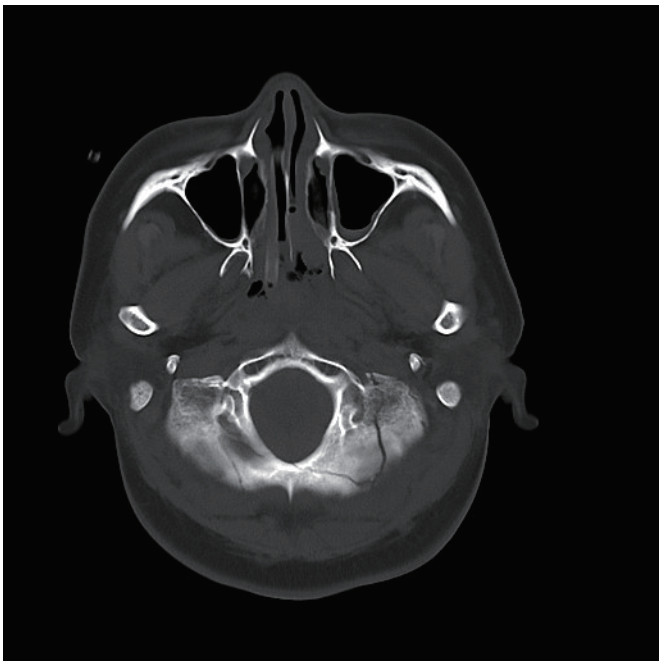

1 病例资料患者,女性,40岁,因“车祸致全身多处外伤半小时余”于2025年6月27日由120送入黄山市人民医院急诊。患者2 h前骑电瓶车发生车祸,致头面部、胸部及左下肢严重受伤,当即昏迷,伴恶心呕吐。入抢救室时自主呼吸微弱,后出现室速,伴随血流动力学不稳定,GCS评分为6分(E1V1M4),双侧瞳孔不等大、对光反射迟钝,左侧直径3 mm,右侧5 mm,后枕部头皮血肿,左下肢胫腓骨区域明显肿胀畸形。医院立即实施全面评估,经紧急行电复律、利多卡因静推后恢复自主心率,予以气管插管保护气道,建立深静脉通路泵入血管活性药物维持血压、纠正酸中毒。完善CT检查:双侧脑挫伤、创伤性蛛网膜下出血、右侧额顶部硬膜下血肿,中颅底及枕骨骨折、累及枕骨大孔,左侧胫腓骨骨折及双肺坠积性改变。见图 1,2。神经外科会诊诊断为弥漫性轴索损伤,无立即手术指征,收入EICU监护稳定生命体征。

| 图 2 枕骨骨折 |